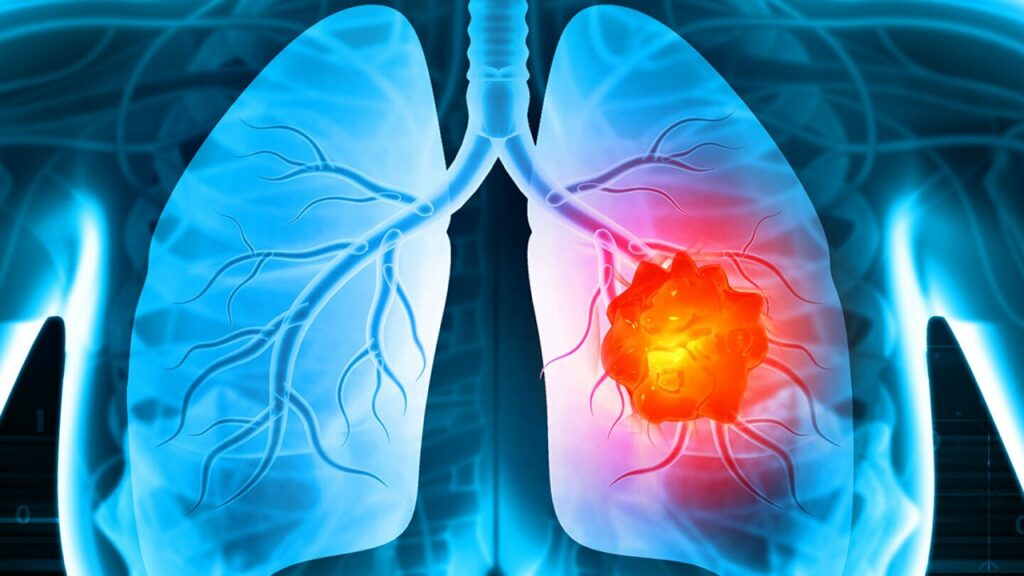

سرطانها روال درمانی سخت و طویل دارند. سرطان ریه هم یکی از طاقتفرساترین بیماریها است که با وجود پیشرفتهای تازه در درمان آن، تا این مدت هم فرایند درمان پیچیدهای دارد. این سرطان زیاد تر جواب خوبی به داروهای شیمیایی نمیدهد. بااینحال، محققان دانشگاه کلمبیا راهحلی بالقوه را اراعه دادهاند: درمان استنشاقی IL-12 mRNA.

این مطالعه نشان داد که استنشاق حاملهای طبیعی برای ساخت مولکول ایمنی (IL-12 mRNA) در درمان سرطان ریه موشها زیاد مؤثر است.

منفعت گیری از وزیکولهای خارج سلولی (EVs) بهتر از درمانهای دیگر عمل کرد و تبدیل کوچکترشدن تومورها، بقای طویلتر موشها و جوابهای ایمنی نیرومندتر شد.

این درمان علتدعوا قوی سیستم ایمنی به تومورها شد؛ این چنین افزایش تشکیل یک مولکول ایمنی کلیدی به نام «IFNγ» و سلولهای کشنده نیرومندتر «CD8+ T و NK» را بههمراه داشت.